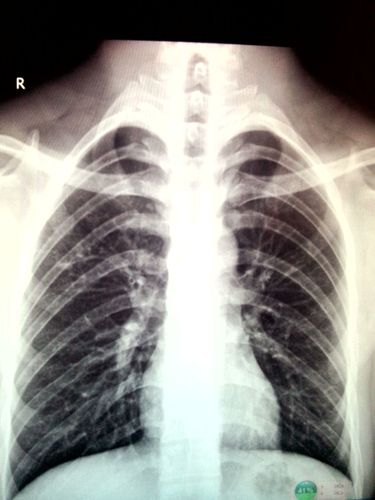

肺结核咳出坏死物图片

肺结核

空洞型肺结核

肺结核ct

肺结核图片

肺结核x光片